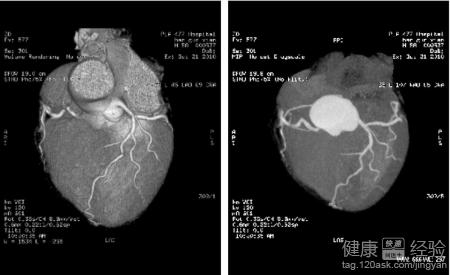

3第三,心髒冠狀動脈血管成像CT(CTA),冠脈造影:若患者出現胸悶、胸痛不適,且活動後逐漸加重,可能有心梗復發,可行CTA檢查,若是觀察不明確,可行冠脈造影檢查,進一步明確病因。

第3步